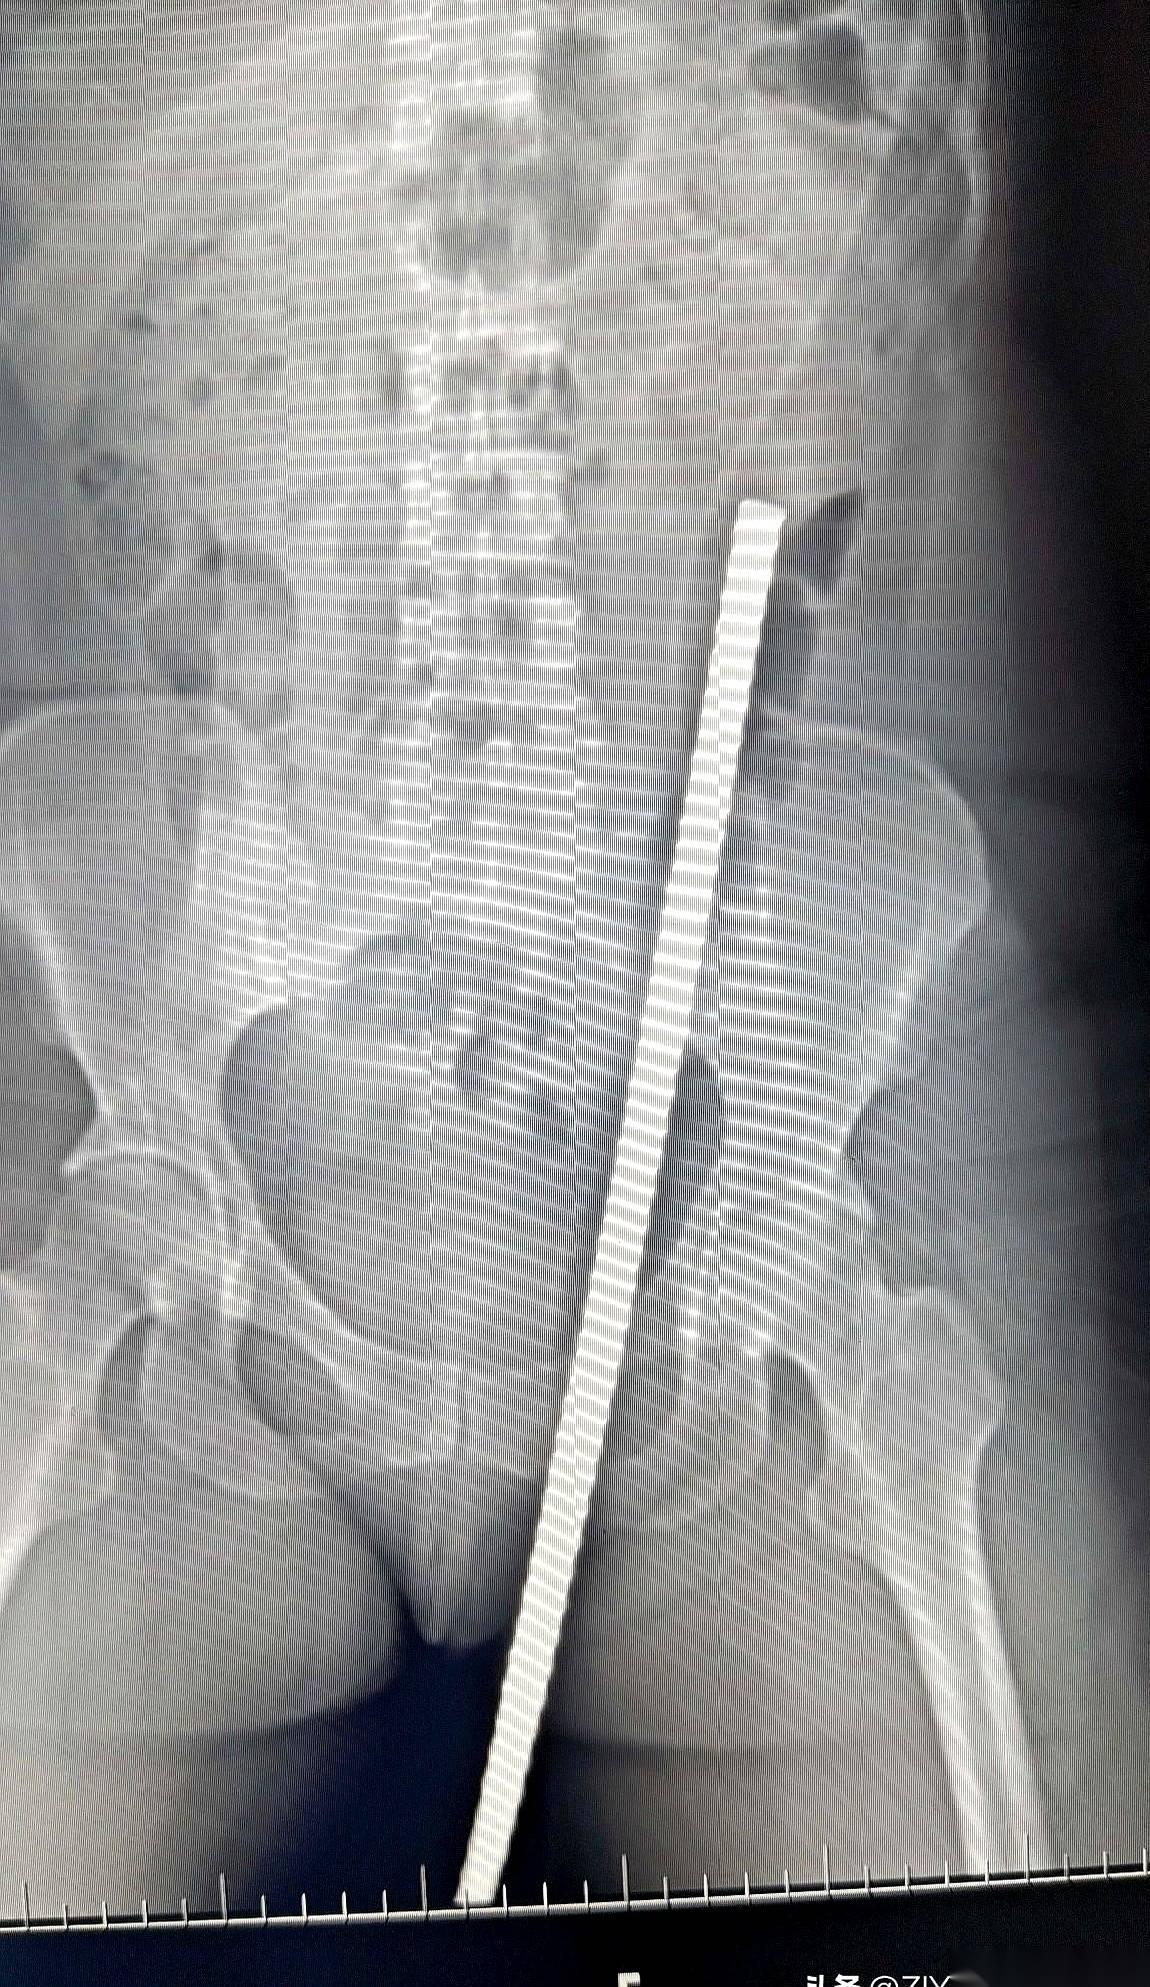

急诊室的门一推开,所有人的声音都小了下去。 担架上躺着一个女人,47岁,工地上干活的。一根粗钢筋,从她身体下方贯穿,从另一头的腹部皮肤顶了出来。人是清醒的,但脸上没有一丝血色,嘴唇抖得说不出话。 没人敢碰那根钢筋。谁都清楚,这玩意只要偏一毫米,里面就是肠子、大血管。现在拔,等于亲手送她走。 检查室里,气氛凝重得像块铁。医生们盯着CT机,等着那个最终的“判决书”。机器嗡嗡作响,屏幕上,一帧一帧的黑白影像缓缓生成。 所有人都凑了过去,死死盯着那条刺眼的金属白线。 它进去了。斜着向上。然后,就在快要碰到一堆要命的器官时,它拐了个弯,贴着内壁,硬生生从脂肪层里挤出了一条路,最后从肚皮下钻了出来。 就差那么一点点。 一名老医生摘下眼镜,反复擦了擦,又戴上,再看一遍。没错,钢筋完美地避开了所有脏器。那个救了她命的东西,是她厚厚的脂肪。 这层平时可能让她烦恼的脂肪,像个垫子,硬是把死神的刀给隔开了。 只能说,有时候,你身上最嫌弃的东西,恰恰是你的保命符。